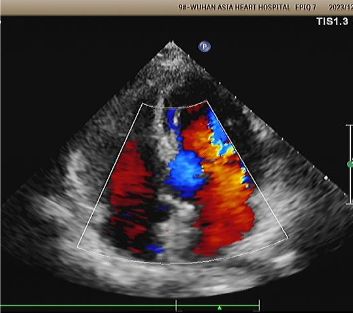

Echo di 1 anno:

No visible disc structures – replaced by 8mm tissue thickening at the septal implant site.

Zero residual shunt (rest or post-Valsalva).

Assorbimento completo del dispositivo confermato.